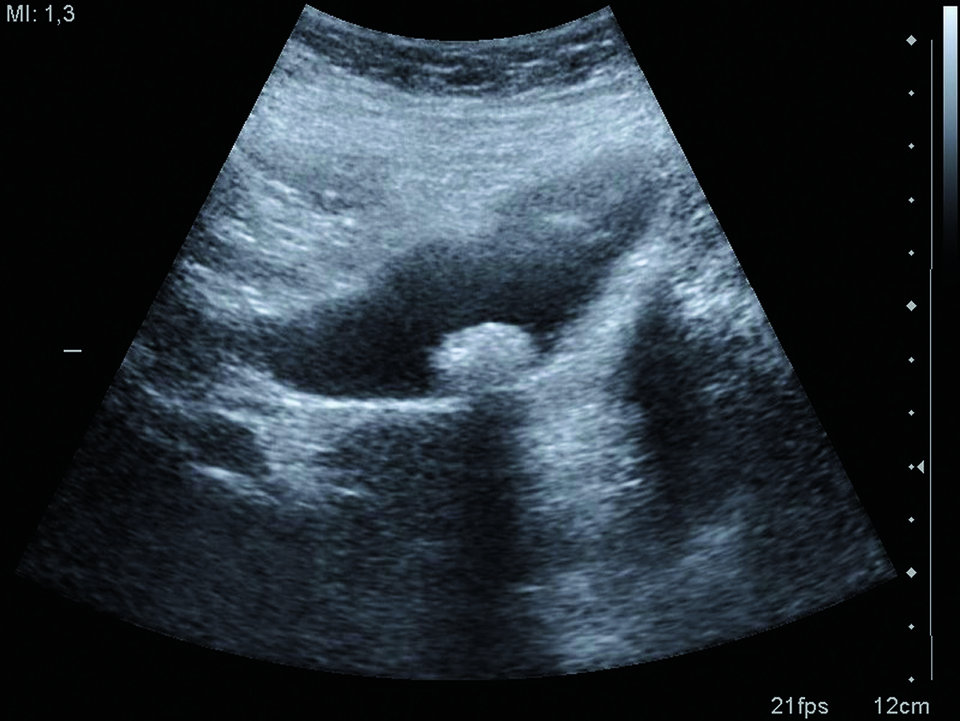

Beim Abklären mutmaßlich biliär bedingter Schmerzen muss auf Ikterus, Fieber, Schüttelfrost und mögliche Symptome einer Pankreatitis geachtet werden. Die Labor­analyse sollte Gesamtbilirubin, Gamma-Glutamyltransferase (­γ-GT), alkalische Phosphatase (AP), die Lebertransaminasen AST und ALT, Lipase und Entzündungsparameter umfassen. Hinzu kommt eine transabdominelle Oberbauchsonographie, um Veränderungen von Gallenblase und Gallenwegen erfassen zu können. Das weitere Vorgehen hängt davon ab, wie wahrscheinlich das gleichzeitige Vorliegen von Cholezysto- und Choledocholithiasis ist, und ob Hinweise für Cholangitis oder biliäre Pankreatitis bestehen.

Ein erweiterter extrahepatischer Gallengang in der Sonographie bei gleichzeitiger Hyperbilirubinämie und erhöhten Leberwerten (­γ-GT, AP, ALT, AST), Gallengangskonkrementen sowie klinische oder laborchemische Kriterien für eine aszendierende Cholangitis deuten auf eine hohe Wahrscheinlichkeit (> 50 %) für das gleichzeitige Bestehen von Cholezys­to- und Choledocho­lithiasis hin. Bei mittelhoher Wahrscheinlichkeit (5–50 %) sollte die Beteiligung des Gallengangs mittels Endo­sonographie oder Magnetresonanz-­Cholangio­pankreatikographie (MRCP) geklärt werden. Ist eine Gallengangsbeteiligung wahrscheinlich, folgt die endoskopische retrograde Cholangiographie (ERC) mit Sphinkterotomie und Steinextraktion beziehungsweise die Anlage einer ­Drainage. An die endoskopische Gallengangssanierung sollte sich die Cholezystektomie innerhalb von 72 Stunden anschließen. Die Kriterien, die für eine Cholangitis sprechen, fasst man in drei Gruppen zusammen:

• sonographischer Nachweis eines erweiterten Gallengangs (> 7 mm), von Konkrementen oder anderer Abflusshindernisse